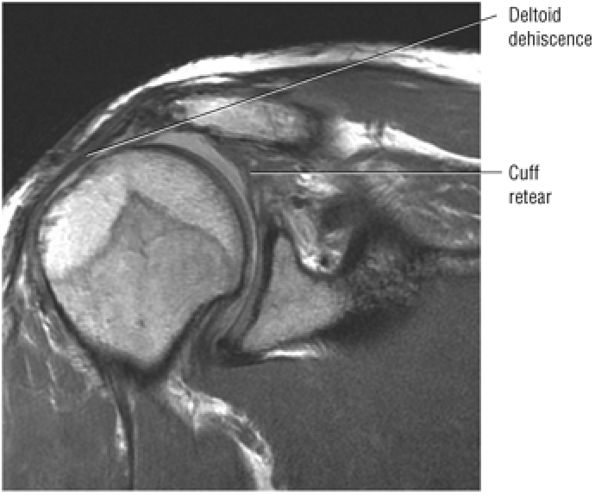

FIGURE 8.102 ● (A) The anterior undersurface of the acromion and the coracoacromial ligament form the coracoacromial arch. The subacromial subdeltoid bursa facilitates the passage of the rotator cuff and proximal humerus under the coracoacromial arch. (B) A superior axial image shows the anterior-to-posterior extent of the coracoacromial (CA) ligament perpendicular to the supraspinatus tendon. The fluid in the subacromial-subdeltoid bursa represents fluid between two serosal surfaces in contact with each other. One serosal surface is contributed by the undersurface of the coracoacromial arch and deltoid, and the other serosal surface is on the bursal side of the cuff.

|

![]() |